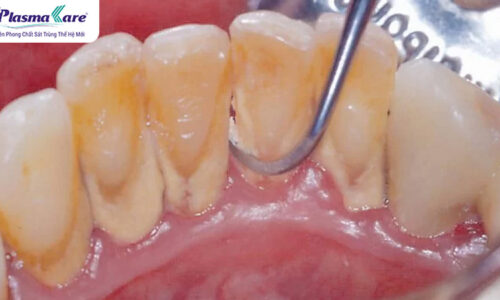

Cao răng là lớp mảng bám cứng hình thành theo thời gian mà nhiều người thường xem nhẹ vì không gây đau nhức tức thì. Tuy nhiên, chính sự tồn tại âm thầm này lại là khởi nguồn của hàng loạt vấn đề răng miệng nghiêm trọng như viêm nướu, viêm lợi, nha chu, tụt lợi và nguy cơ mất răng sớm.

Câu trả lời là CÓ. Lấy cao răng là một thủ thuật nha khoa cần thiết và nên thực hiện định kỳ để bảo vệ sức khỏe răng miệng. Cao răng là mảng bám đã bị khoáng hóa, bám chặt vào bề mặt răng và dưới nướu, không thể loại bỏ hoàn toàn bằng việc đánh răng thông thường. Nếu không được làm sạch kịp thời, cao răng sẽ trở thành ổ vi khuẩn gây viêm nướu, viêm quanh răng và nhiều biến chứng nghiêm trọng khác.

- Ngăn ngừa viêm lợi, viêm quanh răng: Cao răng tích tụ lâu ngày gây kích ứng mô nướu, dẫn đến sưng đỏ, chảy máu chân răng và viêm nhiễm. Việc cạo vôi định kỳ giúp loại bỏ vi khuẩn gây hại, hạn chế nguy cơ tiến triển thành viêm nha chu – nguyên nhân hàng đầu gây tiêu xương và mất răng.

- Bảo vệ chân răng, ngăn ngừa tình trạng răng lung lay: Cao răng bám quanh cổ răng và dưới nướu có thể làm nướu tụt, lộ chân răng và làm giảm độ bám chắc của răng. Lấy cao răng đúng cách giúp duy trì mô quanh răng khỏe mạnh, từ đó hạn chế nguy cơ răng lung lay và rụng sớm.

- Tăng tính thẩm mỹ cho nụ cười: Cao răng thường có màu vàng nâu hoặc đen, khiến răng xỉn màu và kém sạch sẽ. Sau khi lấy cao răng và đánh bóng, bề mặt răng trở nên nhẵn mịn, sáng hơn, giúp nụ cười trông tươi tắn và tự nhiên hơn.